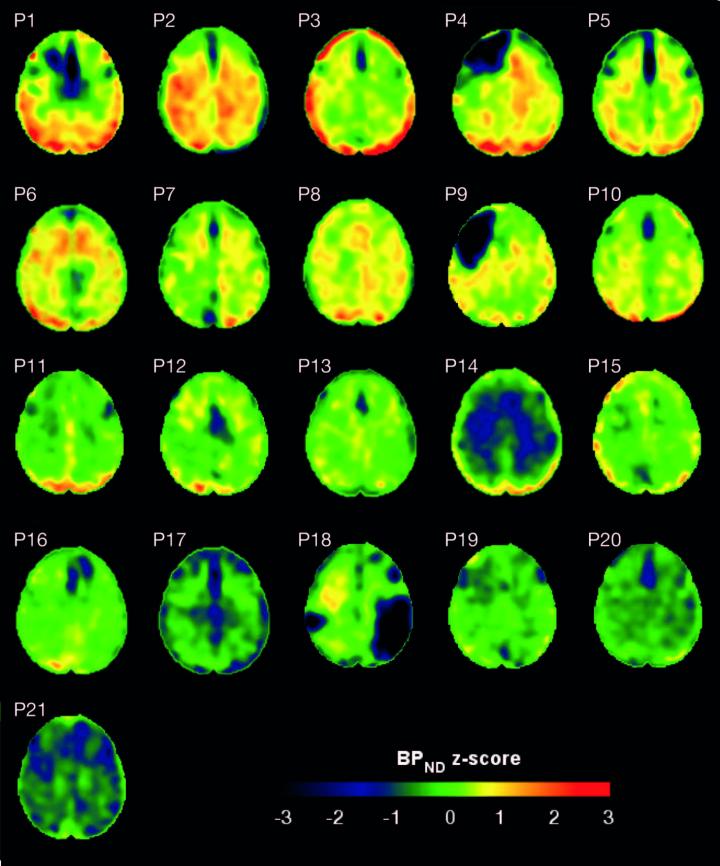

image: Maps showing the concentrations of tau protein (BP-ND z-score) in the brains of patients with traumatic brain injury and healthy controls. This material relates to a paper that appeared in the Sep. 5, 2019, issue of Science Translational Medicine, published by AAAS. The paper, by N. Gorgoraptis at Imperial College London in London, UK; and colleagues was titled, "In vivo detection of cerebral tau pathology in long-term survivors of traumatic brain injury."

A single incidence of traumatic brain injury (TBI) can lead to long-lasting neurodegeneration, according to a study of 32 individuals. In addition to clarifying the little-understood chronic effects of TBI, the study's methods could improve the diagnosis and monitoring of brain damage in patients who have suffered an injury. Research has shown that TBI can trigger progressive accumulation of tau, a protein associated with neurodegeneration that plays a major role in Alzheimer's disease. Scientists have studied the effects of TBI by combining PET imaging with flortaucipir, an imaging agent that binds to tau. Most imaging studies have been performed in athletes who have experienced multiple injuries, but it is less clear how the brain changes in survivors who experienced a single TBI. Nikos Gorgoraptis and colleagues performed flortaucipir PET scans to study the distribution of tau in 21 participants who experienced a TBI at least 18 years prior, due to either traffic accidents or assault. The experiment revealed that collectively, the TBI cohort showed more deposition of tau (as indicated by higher flortaucipir binding) compared to 11 healthy controls and performed more poorly on tests of memory and cognitive performance. Furthermore, TBI subjects with higher tau deposition showed more severe neurodegeneration, and tau deposition was also linked to damage to the brain's white matter - the tissue that insulates and nurtures neurons. The ability to detect tau in patients after TBI could help in the design of future trials of tau-targeting therapies, the authors add.